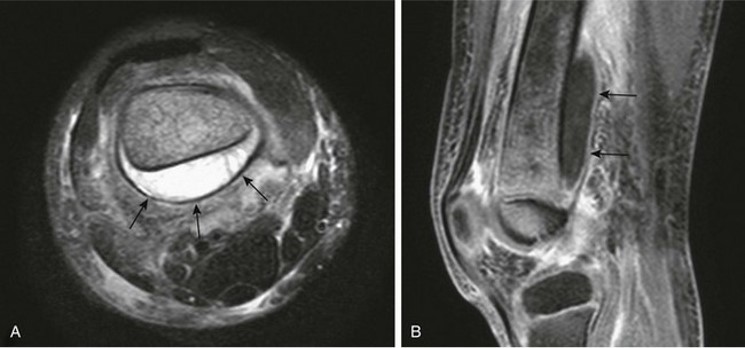

subperiosteal abscess.

happens in peds, Periosteum is loose in pediatrics and bone infection decompresses in the subperiosteal space